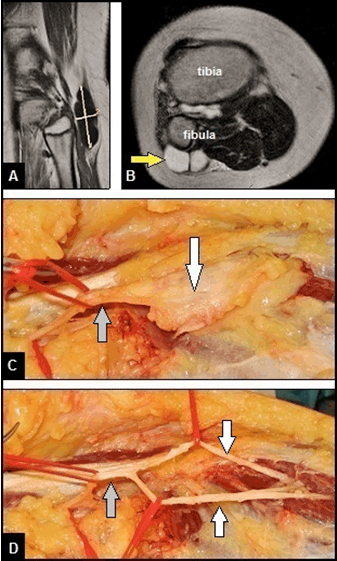

An 11-year-old obese boy presented with a right common peroneal nerve (CPN) palsy. At first presentation in our hospital, the patient reported progressive palsy starting only with painless weakness for dorsiflexion of his right foot two years ago. There was no history of any trauma. Within these two years, the patient was explored by his family doctor, a pediatrics, and a neurologist. The diagnostic management included magnetic resonance imaging (MRI) of the cerebrum and overall spine, electromyography, electroencephalography, analyses of blood and cerebrospinal fluid samples. No causes could be found by the treating physicians that declared his CPN palsy. So the diagnosis of a peroneal nerve mononeuropathy with unclear genesis was made, and the patient was treated by oral medication of glucocorticoids and vitamin B12. On first clinical examination in our hospital, a painless foot drop was present, and the sensibility at the peripheral peroneal nerve area was completely lost. The strength of dorsiflexion of foot was completely lost according grade 0 in Medical Research Council scale (0–5), and electromyography revealed a severe axonal lesion in the absence of motor activities. Magnetic resonance imaging (MRI) scans of his right knee revealed a subcutaneous, well demarcated and lobulated cyst adjacent to the proximal tibiofibular joint which was clinically not palpable through the thick layer of subcutaneous fat of the obese patient (Figure 1A–B). According to these findings, the diagnosis of a proximal tibiofibular joint cyst was made by the radiologist. Based on the presented peripheral neurological symptoms, surgical revision was detected by us. The lesion was surgically exposed through a large longitudinal incision starting distally over the lateral aspect of fibula, passing the popliteal fossa with a vertical incision, and extending up longitudinally on the dorsal aspect of the thigh. Intraoperatively, a cyst originating from the proximal tibiofibular joint could not be found, but there was an extraneural and intraneural ganglion cyst with size of 7x2.5 cm involving the CPN, and both its superficial sensory nerve (SSN) and deep motor nerve (DMN) distally (Figure 1C). After careful dissection and removal of the tumor in a monobloc manner, a division of the CPN distally was seen, but macroscopically there were no structural damages (i.e., neurotmesis) both of the CPN and its DMN/SSN (Figure 1D). Histological examination confirmed the diagnosis of a benign ganglion cyst. The wound healing was uneventful. One year after surgery, a functional recovery could not be observed, so a tendon transfer procedure to restore dorsiflexion of his foot was recommended by us, but declined by the parents of the patient at this time.

Figure 1: (Case presentation): (A) Coronar T1-weighted MRI scan demonstrating the well demarcated oval cyst adjacent to the proximal tibiofibular joint, (B) Axial T2-weighted MRI scan demonstrating the subcutaneous lobulated cyst with a signal similar to water lateral to the proximal fibula (arrow), also noted that the cyst is surrounded by a thick layer of subcutaneous fat that did not allow sensing the tumor by palpation, (C) Intraoperative clinical photograph showing the carefully dissected CPN (gray arrow) which is surrounded distally by the oval ganglion cyst with size of 7x2 cm, and (D) Intraoperative clinical photograph after removal of the cyst in a monobloc manner showing that the CPN (gray arrow) was divided distally, and macroscopically there were no structural damages both of the DMN and SSN (white arrows).